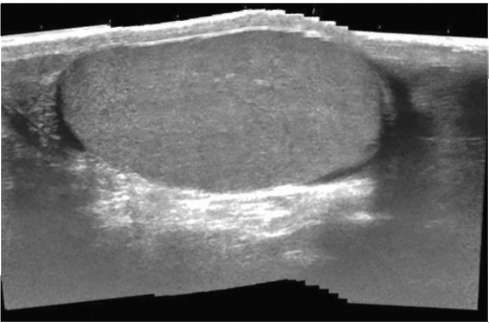

УЗИ почек. Основным доступом при локации почек является кособоковое расположение датчика по средней подмышечной линии. Данная проекция дает изображение почки, сопоставимое с изображением при рентгенологическом исследовании. При сканировании по длинной оси органа почка имеет вид овального образования с четкими, ровными контурами (рис. 4.10).

Рис. 4.10. Сонограмма. Нормальное строение почки

УЗИ органов мошонки. При УЗИ органов мошонки используют датчики высокой разрешающей способности, от 5 до 12 мГц, что позволяет хорошо видеть мелкие структуры и образования. В норме яичко определяется в виде гиперэхогенного образования овальной формы с четкими, ровными контурами (рис. 4.23).

Рис. 4.23. Сонограмма мошонки. Яичко в норме

Структура яичка характеризуется как однородная гиперэхогенная ткань. В центральных отделах его определяется линейная структура высокой плотности, ориентированная по длиннику органа, что соответствует изображению средостения яичка. В краниальных отделах яичка хорошо визуализируется головка придатка, имеющая форму, близкую к треугольной. К каудальному отделу яичка прилежит хвост придатка, повторяющий форму яичка. Тело придатка визуализируется неотчетливо. По своей эхогенности придаток яичка близок к эхогенности самого яичка, однороден, имеет четкие контуры. Межоболочечная жидкость анэхогенная, прозрачная, в норме определяется в виде минимальной прослойки от 0,3 до 0,7 см преимущественно в проекции головки и хвоста придатка.